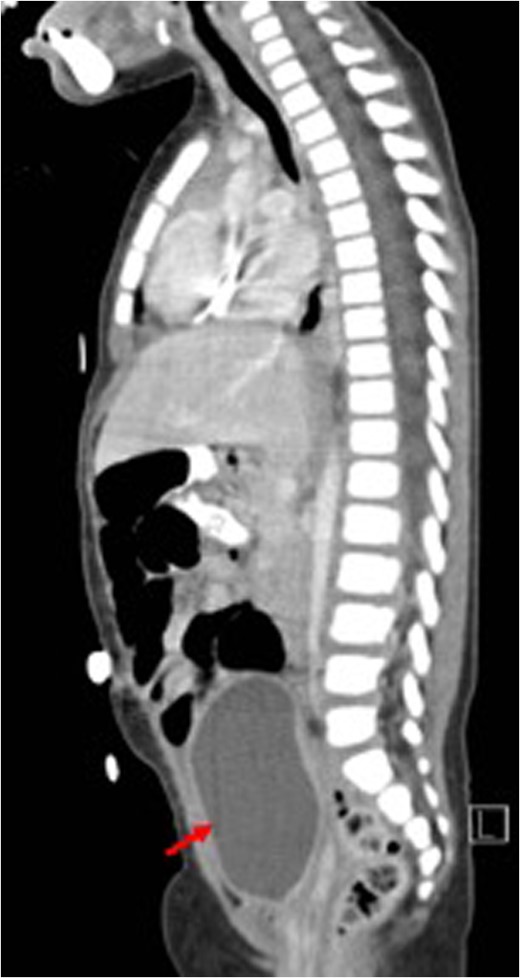

Post-treatment sagittal view (CT) with no evidence of recurrence arising from the uterus (red arrow) bladder.